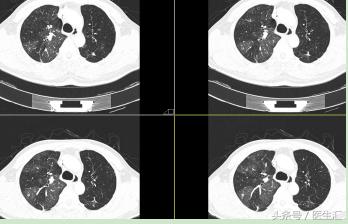

CT 图片示:

患者右肺肺野密度不对称,左肺尚可,出现的是 “马赛克征”。可考虑:小气道病变或肺栓塞。

P.S :“马赛克”征是肺小气道病变时高分辨力CT或薄层CT所示的一种非特异性征象。表现为肺密度不均匀,补丁状的异常透光区+斑片状的磨玻璃密度影镶嵌存在,形似“马赛克”。